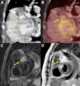

Cardiac tumor

Primary tumors of the heart are extremely rare tumors that arise from the normal tissues that make up the heart. This is in contrast to secondary tumors of the heart, which are typically either metastatic from another part of the body, or infiltrate the heart via direct extension from the surrounding tissues. [Source: Wikipedia ]